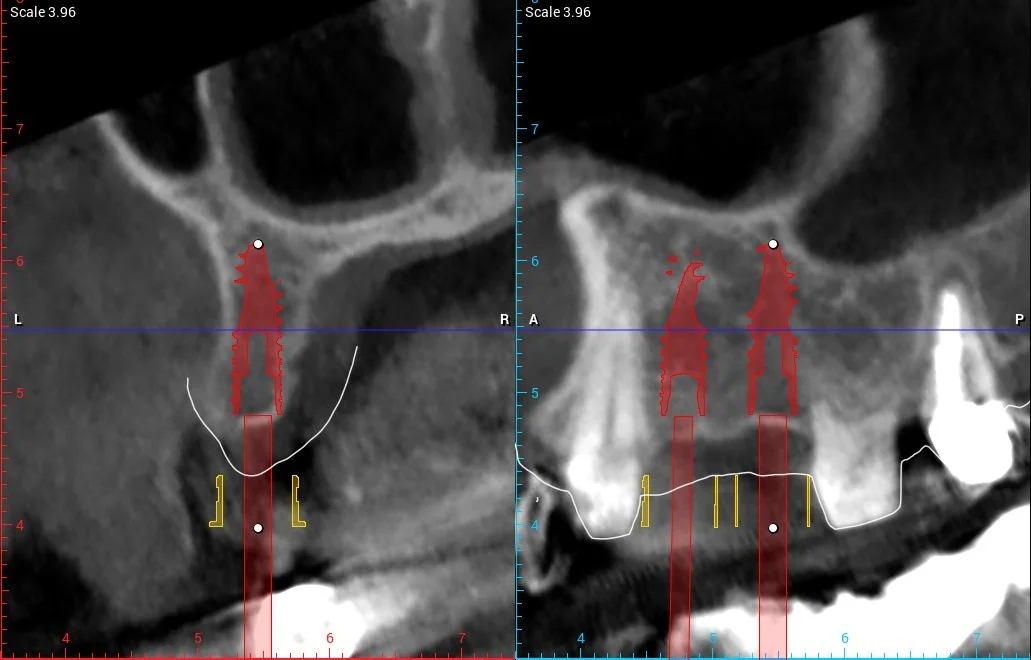

A 3D X-ray (CBCT) was taken to check the bone

We digitally designed the final shape of the new teeth

A digital scan of the teeth was done (no messy impressions)

The scan showed that the bone space was limited, so the implants had to be placed very accurately.

Using specialized software, the CBCT and intraoral scans were merged into a single digital model. The missing teeth were digitally designed in their ideal position, and two high-quality implants were carefully planned according to the final crowns and available bone — without the need for bone grafting.

A customized digital surgical guide was then designed and 3D-printed using FDA-approved material to ensure exact implant placement during surgery.